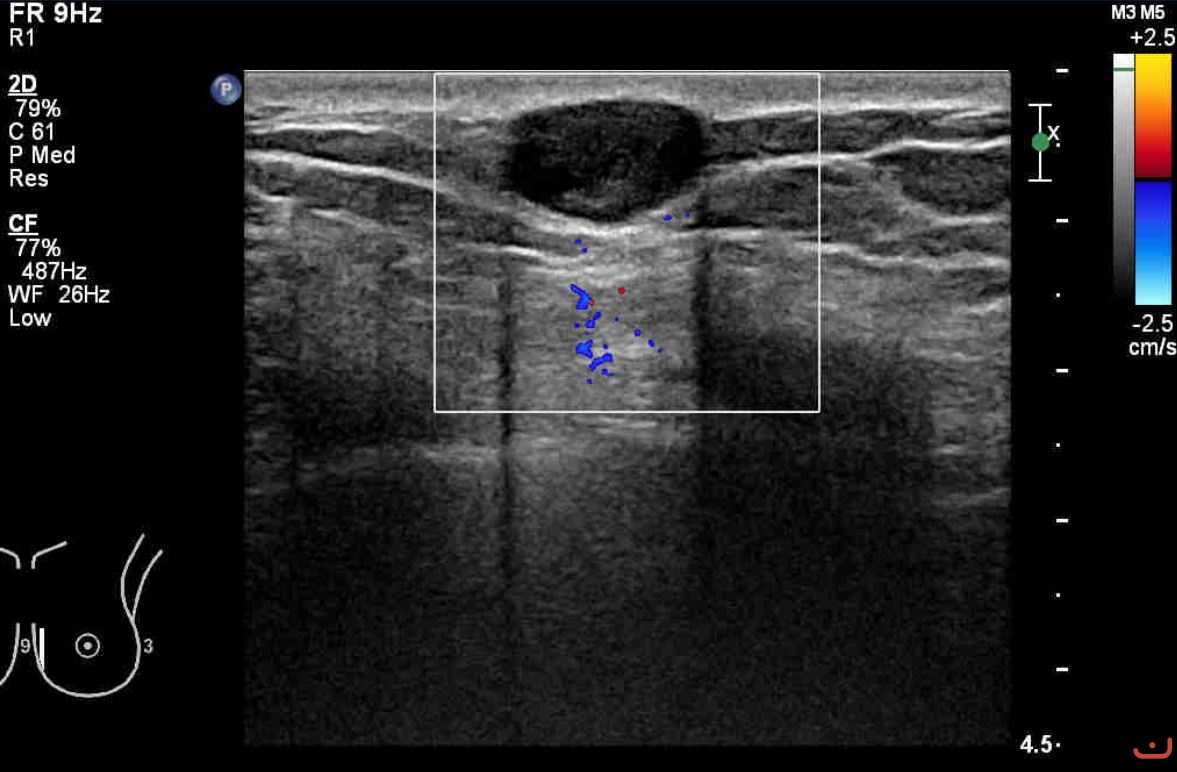

Benign solid mass

Sunday, 16 August 2015